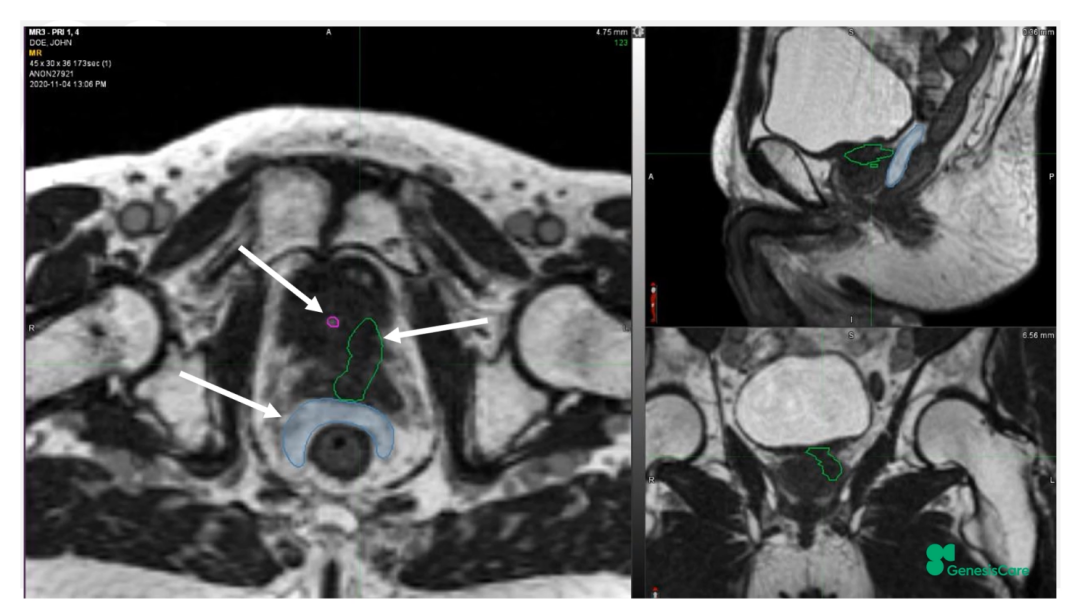

Dr. CamilleriÌåÏÖ£¬£¬£¬£¬£¬£¬ËûÃÇÔÚ×öÔÚÏß×Ô˳Ӧ·ÅÁƵÄʱ¼ä£¬£¬£¬£¬£¬£¬ÎªÁËÌá¸ßËÙÂÊ£¬£¬£¬£¬£¬£¬½ö¶Ô°ÐÇøÍâ·Å3cmÒÔÄÚµÄΣ¼°Æ÷¹ÙµÄת±ä¾ÙÐÐ×Ô˳Ӧµ÷½â»òÖØÐ¹´»ÂÖÀª£¬£¬£¬£¬£¬£¬¼ûFigure 13¡£¡£¡£¡£¡£¡£¡£ÕâÑù¿ÉÒÔËõ¶ÌÂÖÀª¹´»µÄʱ¼ä¡£¡£¡£¡£¡£¡£¡£¹ØÓÚ·ÅÁÆÍýÏ룬£¬£¬£¬£¬£¬Ê¹µÃ95%µÄ°ÐÇøÌå»ý½ÓÊܵ½100%µÄ´¦·½¼ÁÁ¿ÁýÕÖ£¬£¬£¬£¬£¬£¬²¢½«×î´ó¼ÁÁ¿ÏÞÖÆÎª2%µÄ°ÐÇøÌå»ý²»Áè¼Ý´¦·½¼ÁÁ¿µÄ110%£¬£¬£¬£¬£¬£¬ÕâÑù¾ÍÄܰü¹ÜÔÚͼÏñÉϺÜÄÑÏÔʾµÄÄòµÀ²»»á³¬Á¿£¬£¬£¬£¬£¬£¬¼ûFigure 14¡£¡£¡£¡£¡£¡£¡£ÁíÍ⣬£¬£¬£¬£¬£¬ÔÚÖÆ×÷·ÅÁÆÍýÏëʱ£¬£¬£¬£¬£¬£¬½«PTV·ÖΪPTV LOWºÍPTV High£¬£¬£¬£¬£¬£¬PTVºÍΣ¼°Æ÷¹ÙÖØµþµÄ²¿·ÖΪPTV LOW£¬£¬£¬£¬£¬£¬½«PTV LOWµÄ¼ÁÁ¿Ä¿µÄÉ趨ÔÚΣ¼°Æ÷¹ÙµÄÄÍÊܼÁÁ¿ÒÔÏ£¬£¬£¬£¬£¬£¬ÕâÑù¾ÍÄܰü¹ÜΣ¼°Æ÷¹Ù²»³¬Á¿£¬£¬£¬£¬£¬£¬¼ûFigure 15¡£¡£¡£¡£¡£¡£¡£